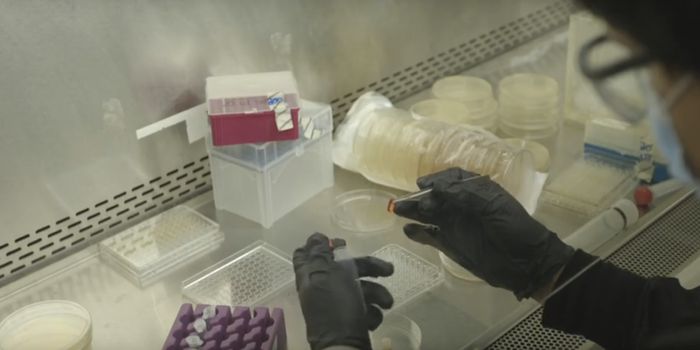

JUN 08, 2021Genetics & GenomicsToday, many scientists are investigating SARS-CoV-2 variants in their research projects. In order to facilitate screenin ...